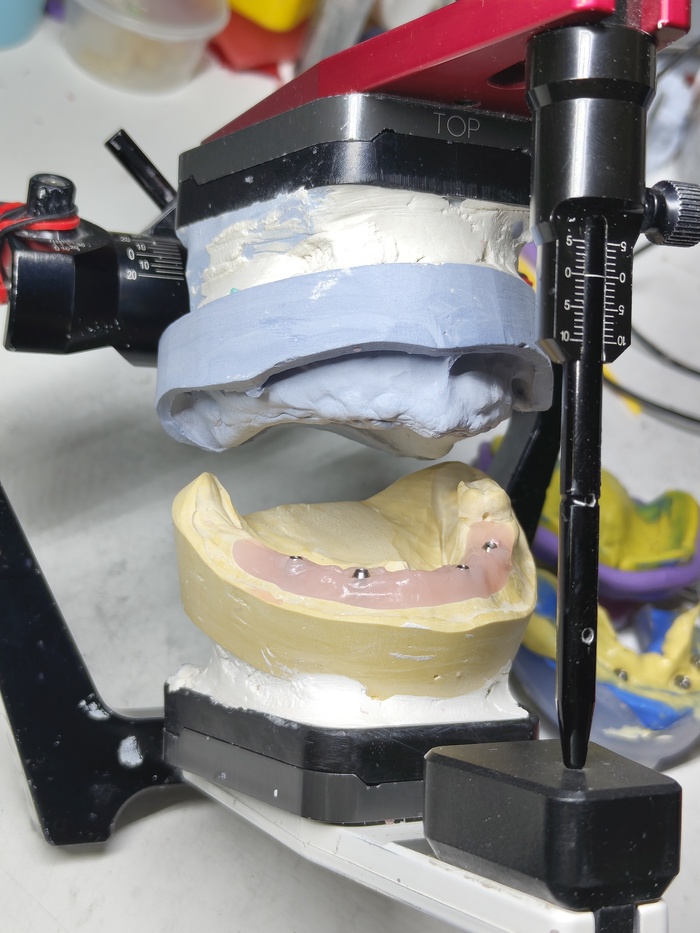

Титановый каркас "сидит" как надо не качается и не балансирует; не только на лабораторной модели, но и в полости рта — можно продолжать.

Хорошо выглядят и блестят, по фото с телефона мало что понятно, но в полости рта они смотрятся гораздо интересней.

Нижний протез плотно, даже с небольшим давлением, прилегает. Верхний через пару месяцев будем делать такой-же.